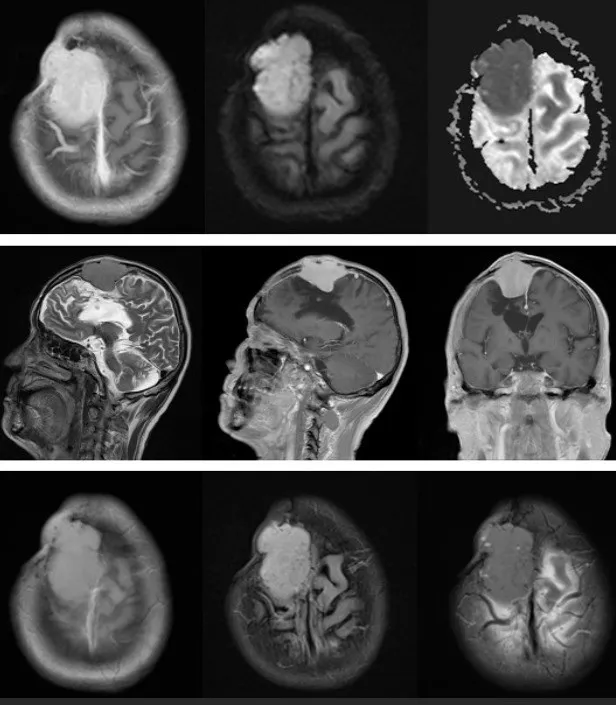

脑膜瘤的一般治疗策略

手术治疗、放疗、化疗、观察随访

是治疗脑膜瘤的常见策略

其中手术是优选的解决办法

切除程度往往也主要影响着治愈率的高低

关于手术作为单一治疗的有效性的证据

来自于医疗机构的病例系列

确定了切除范围(EOR)是一个重要的预后因素

这方面常仍然使用Simpson分类

图:现国际通行的Simpson分级

预测脑膜瘤复发的关系

脑膜瘤手术的基本原则是

进行低并发症发生率和

保护神经功能最大限度的安全切除

虽然切除范围(EOR)是

我们可改变的复发风险因素

但努力实现全切除不应该是

以神经系统或认知功能为代价

脑膜瘤应以手术全切为治疗目标,根据术中情况可接受次全切以保护神经功能,然后定期复查观察残余肿瘤,如果肿瘤小可以选择立体定向放射外科治疗(SRS),若肿瘤增大并出现神经功能缺损症状,应再次显微手术切除肿瘤。